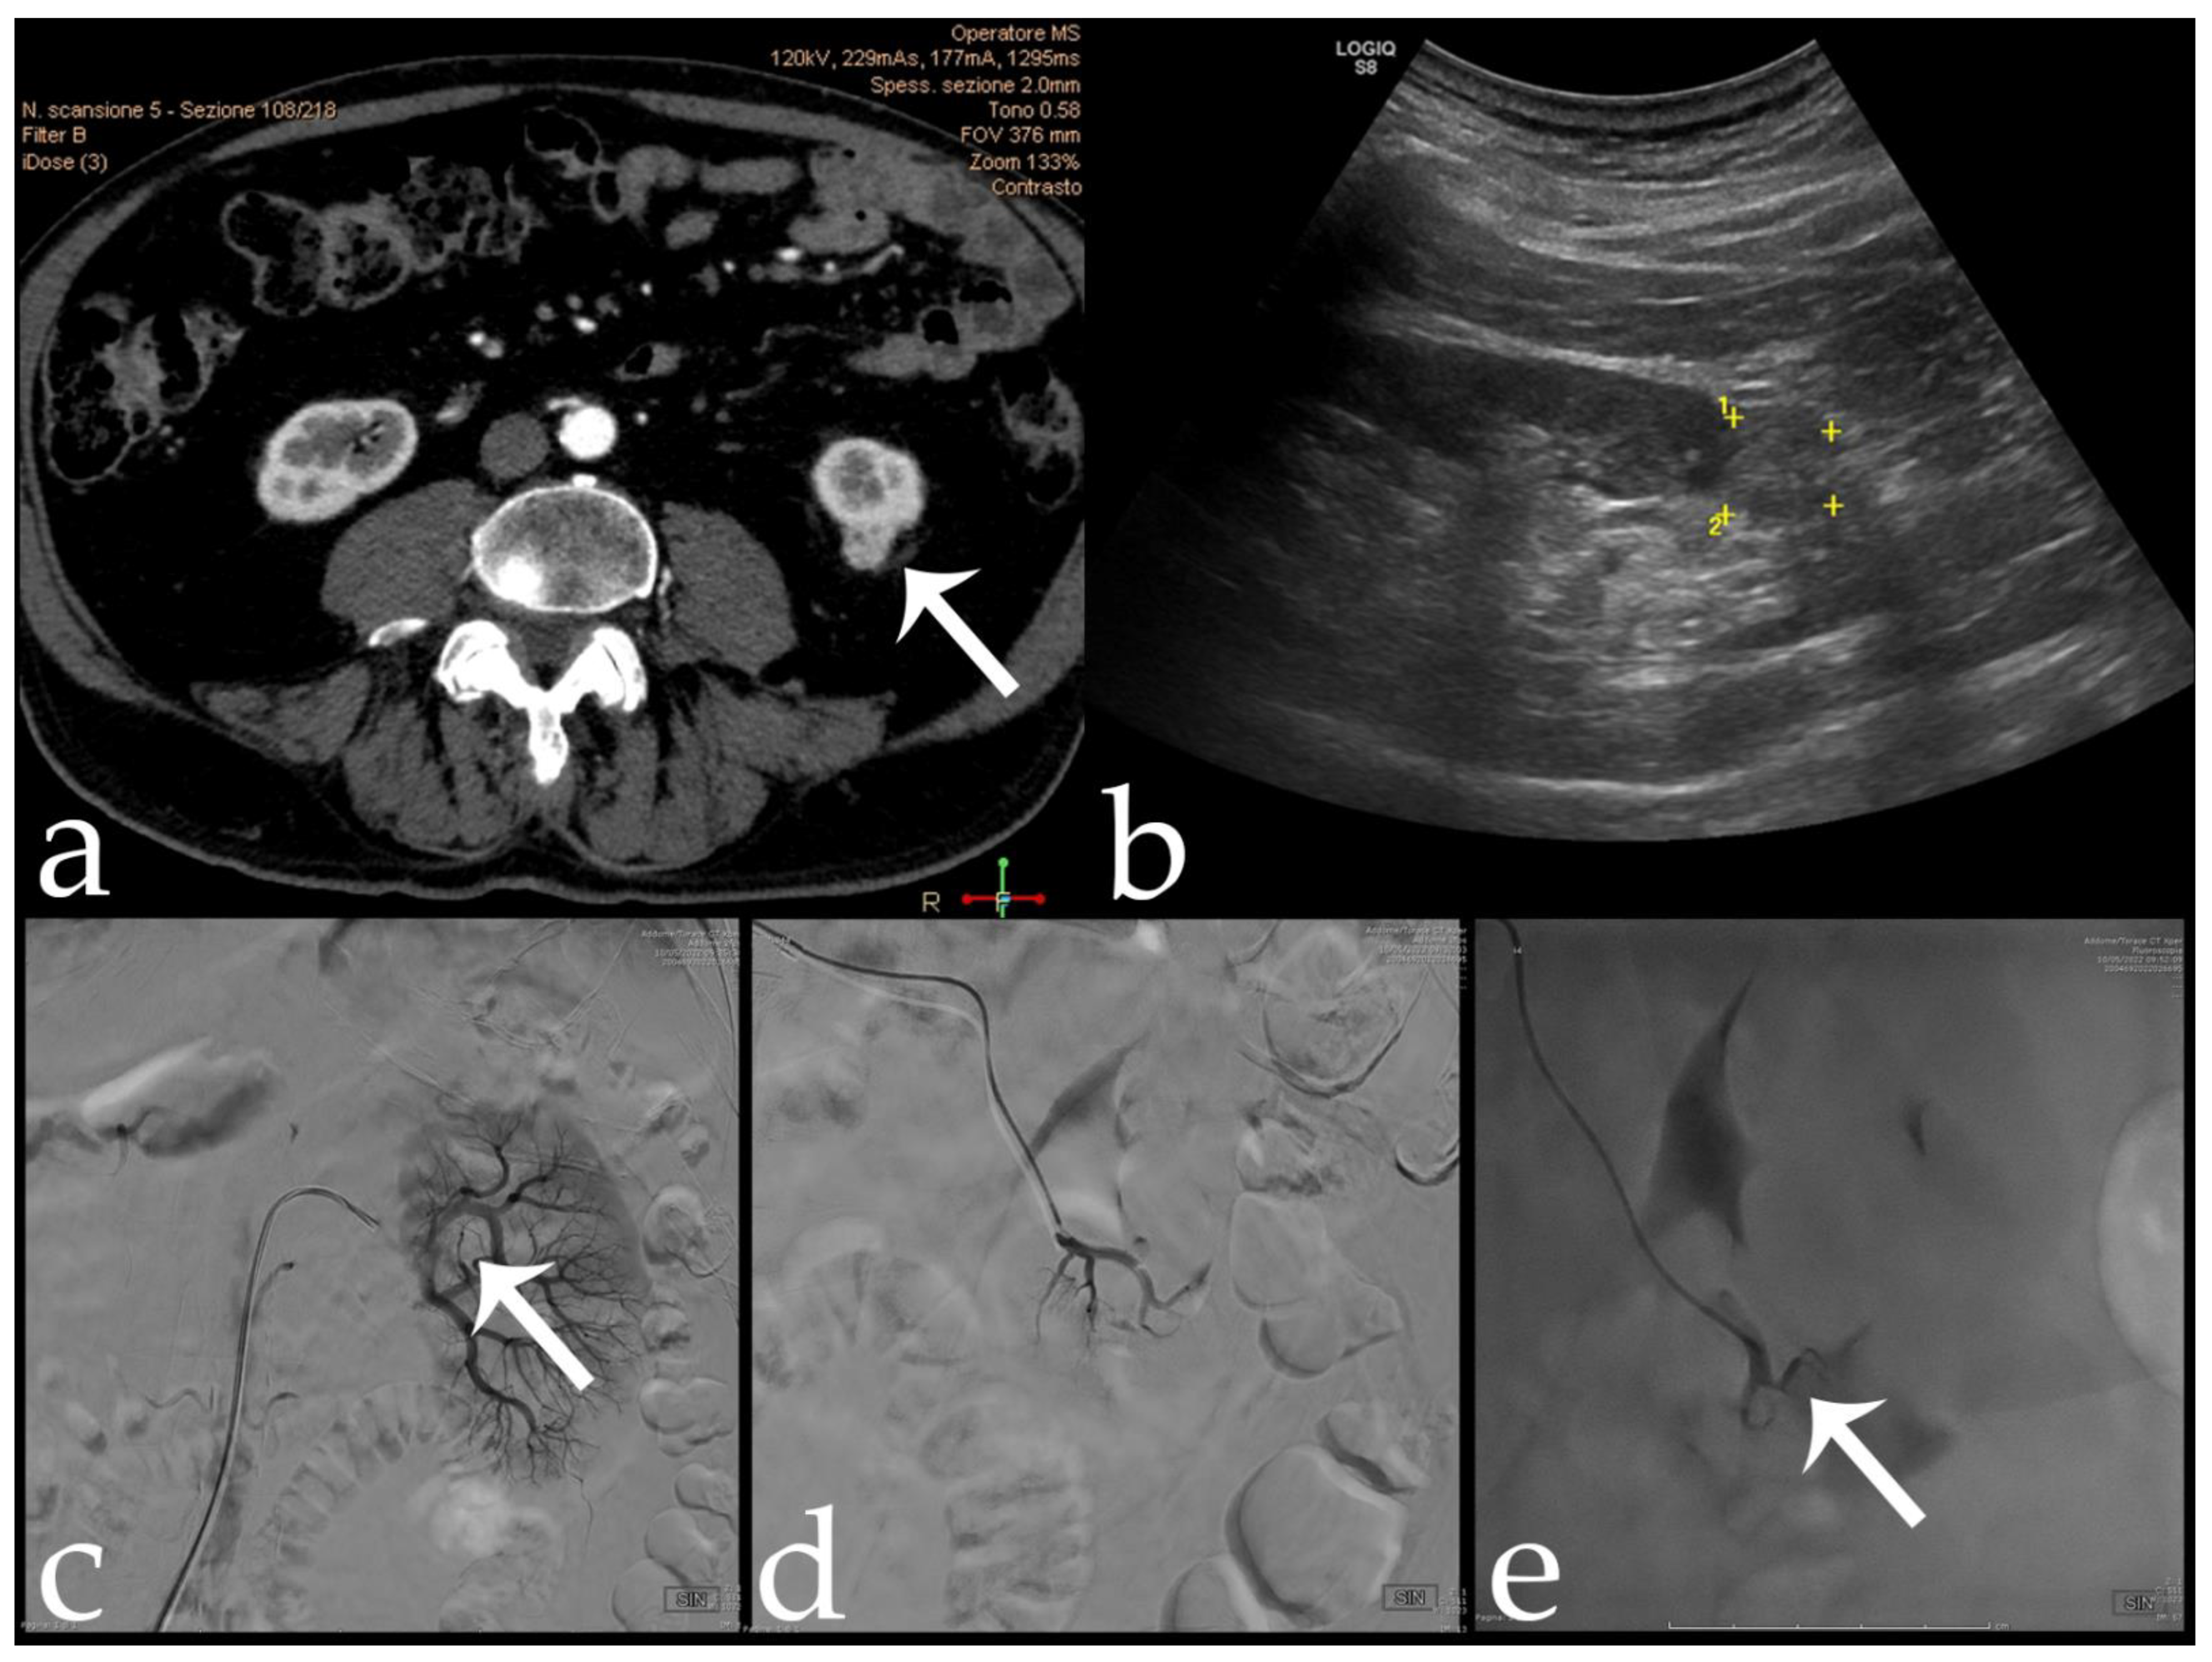

Pre operation